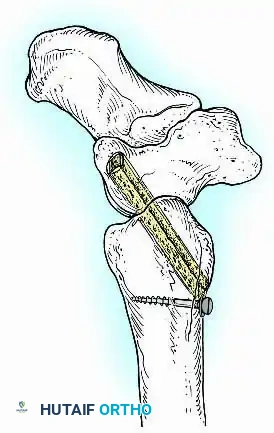

In cases of severe osteopenia or when extending the fusion to the subtalar joint (Tibiotalocalcaneal Arthrodesis), retrograde intramedullary nailing provides a load-sharing construct with superior bending stiffness.

For complex hindfoot reconstructions, specialized plating systems, including anterior or lateral locking plates, can be utilized to supplement screw fixation, particularly when structural allografts are required to restore limb length.

Knee Arthrodesis

While total knee arthroplasty (TKA) is the definitive treatment for knee osteoarthritis, knee arthrodesis remains a critical salvage procedure. The primary indications are a chronically infected TKA that has failed two-stage revision, massive extensor mechanism disruption, severe neuropathic arthropathy, and tumor resection.

Positioning and Technique

The optimal position for knee arthrodesis is 10 to 15 degrees of flexion and 5 to 7 degrees of valgus. This slight flexion assists in foot clearance during the swing phase of gait and makes sitting in confined spaces more manageable. A perfectly straight (0 degrees) knee is cosmetically awkward and functionally detrimental, causing a vaulting gait pattern.